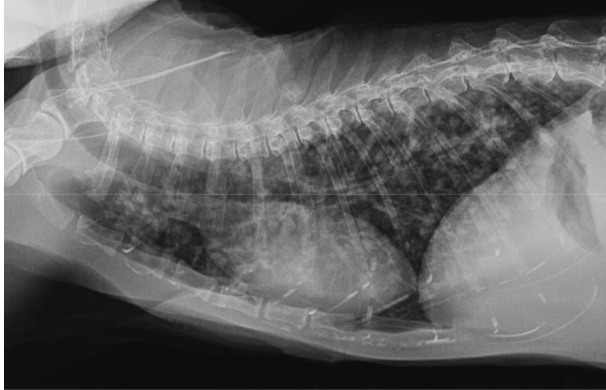

• what pattern can be seen below?

interstitial